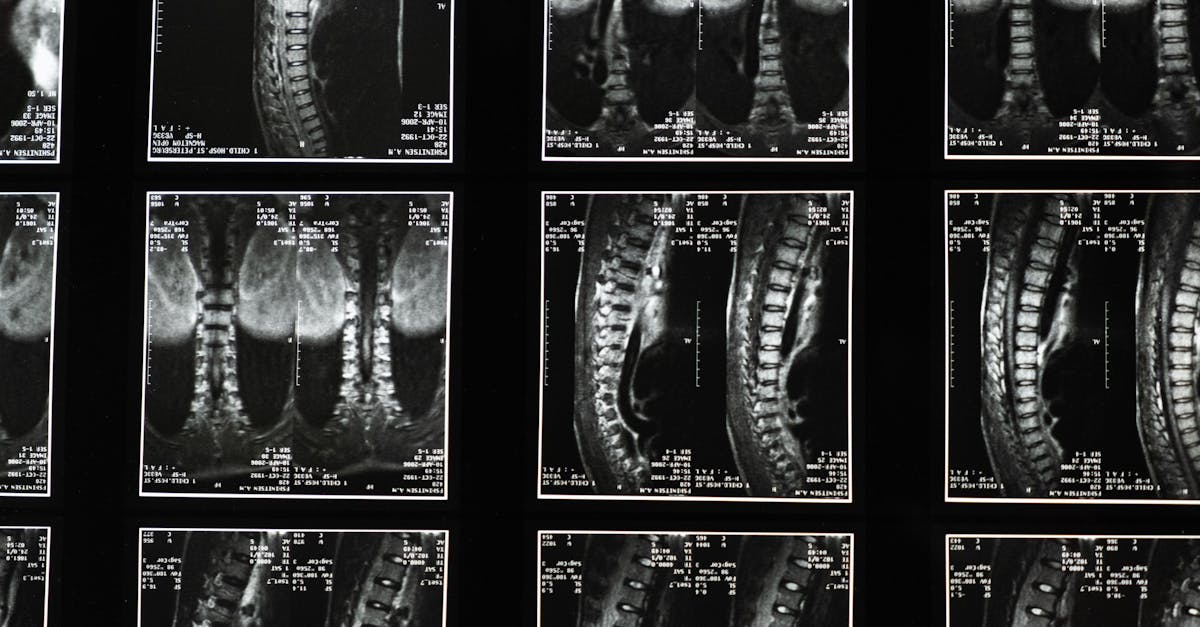

La décompression neurovertébrale est une technique non invasive qui utilise une table de décompression spécialisée pour étirer délicatement la colonne vertébrale. Ce processus crée un vide dans les espaces entre les vertèbres, permettant aux disques intervertébraux de se réajuster et de se réhydrater. Grâce à cette méthode, la pression sur les nerfs épinaux est réduite, ce qui favorise une meilleure circulation sanguine et une diminution de l’inflammation.

La décompression neurovertébrale repose sur des principes scientifiques solidement établis. Ciblant spécifiquement les disques intervertébraux, elle agit pour réduire la pression côté nerveux et optimiser la fonctionnalité de la colonne vertébrale. Avec des études cliniques soutenant son efficacité, cette méthode est reconnue comme une option thérapeutique fiable pour les patients souffrant de sténose spinale.

La décompression neurovertébrale est une méthode thérapeutique innovante qui se concentre sur le traitement des affections de la colonne vertébrale, notamment la sténose spinale. La sténose spinale se caractérise par un rétrécissement du canal rachidien, ce qui peut exercer une pression sur les nerfs et entraîner des douleurs, des engourdissements et une perte de mobilité. Grâce à la décompression neurovertébrale, il est possible de soulager ces symptômes et d’améliorer la qualité de vie des patients souffrant de cette condition.

La décompression neurovertébrale agit en ciblant spécifiquement les disques intervertébraux qui jouent un rôle crucial dans la fonctionnalité de la colonne vertébrale. En réduisant la pression sur ces disques, il est possible de diminuer les douleurs provoquées par la sténose spinale, notamment les douleurs lombaires et cervicales. De plus, cette technique améliore également la flexibilité et la mobilité du patient, contribuant ainsi à un retour à un mode de vie actif et confortable.